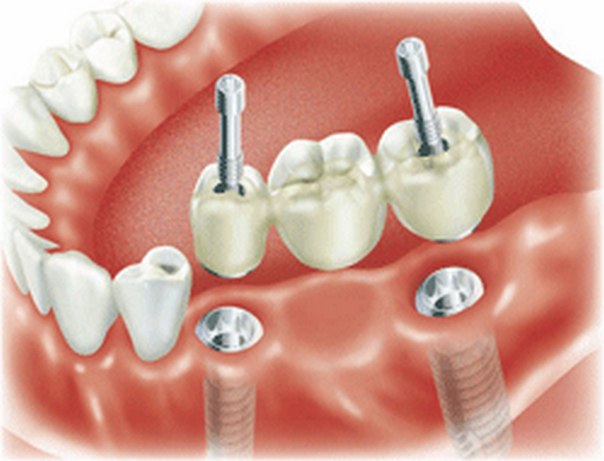

Современные коронки на зубные импланты: виды и фото-примеры